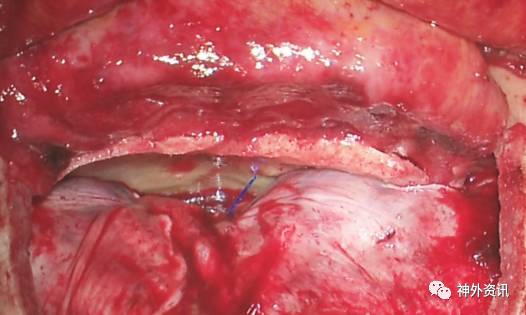

图11. 在肿瘤完全切除、采用颞肌筋膜瓣修复硬脑膜缺损使其完全闭合后,颅底可见一大的骨质缺损。本图上部显示的是完整的骨膜瓣。

图12. 如果术者希望通过双额入路抵达完全位于硬膜内的肿瘤,比如脑膜瘤,于平行骨缘方向切开硬脑膜(A和B)。上矢状窦前部用0号丝线间断结扎,然后离断。尽管矢状窦旁前部的桥静脉被认为是不重要的,但术者在牺牲它们的过程中仍要小心。吸引器头端清晰可见肿瘤组织(C)。缺损的硬脑膜采用一块颞肌筋膜瓣完全封闭,额窦利用骨膜瓣覆盖(D和E)。